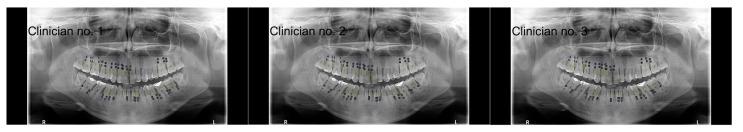

: Periodontitis is a multifactorial disease leading to the loss of clinical attachment and alveolar bone. The diagnosis of periodontitis involves a clinical examination and radiographic evaluation, including panoramic images. Panoramic radiographs are cost-effective methods widely used in periodontitis classification. The remaining bone height (RBH) is a parameter used to assess the alveolar bone level. Large language models are widely utilized in the medical sciences. ChatGPT, the leading conversational model, has recently been extended to process visual data. The aim of this study was to assess the effectiveness of the ChatGPT models 4.5, o1, o3 and o4-mini-high in RBH measurement and tooth counts in relation to dental professionals' evaluations. : The analysis was based on 10 panoramic images, from which 252, 251, 246 and 271 approximal sites were qualified for the RBH measurement (using the models 4.5, o1, o3 and o4-mini-high, respectively). Three examiners were asked to independently evaluate the RBH in approximal sites, while the tooth count was achieved by consensus. Subsequently, the results were compared with the ChatGPT outputs. : ChatGPT 4.5, ChatGPT o3 and ChatGPT o4-mini-high achieved substantial agreement with clinicians in the assessment of tooth counts (κ = 0.65, κ = 0.66, κ = 0.69, respectively), while ChatGPT o1 achieved moderate agreement (κ = 0.52). In the context of RBH values, the ChatGPT models consistently exhibited a positive mean bias compared with the clinicians. ChatGPT 4.5 was reported to provide the lowest bias (+12 percentage points (pp) for the distal surfaces, width of the 95% CI for limits of agreement (LoAs) ~60 pp; +11 pp for the mesial surfaces, LoA width ~54 pp). : ChatGPT 4.5 and ChatGPT o3 show potential in the assessment of tooth counts on a panoramic radiograph; however, their present level of accuracy is insufficient for clinical use. In the current stage of development, the ChatGPT models substantially overestimated the RBH values; therefore, they are not applicable for classifying periodontal disease.

该分析基于10张全景图像,从中分别有252、251、246和271个邻面部位符合RBH测量条件(分别使用4.5、o1、o3和o4-mini-high模型)。三名检查人员被要求独立评估邻面部位的RBH,而牙齿计数则通过协商达成一致。随后,将结果与ChatGPT的输出进行比较。